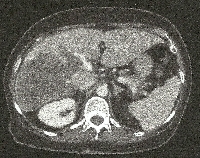

Πρόκειται για γυναίκα ασθενή 63 ετών που, στα πλαίσια διερεύνησης άτυπων κοιλιακών ενοχλημάτων και τρανσαμινασαιμίας, διαπιστώθηκε ότι έπασχε από αποφρακτικό αδενοκαρκίνωμα του σιγμοειδούς με σύγχρονες πολλαπλές (type II) ηπατικές μεταστάσεις (εικόνες 1 & 2). Ο περαιτέρω έλεγχος σταδιοποίησης ήταν αρνητικός για εξωηπατικές μεταστάσεις. Υιοθετήθηκε η κλασσική προσέγγιση (classic approach) αντιμετώπισης της νόσου με βάση το ακόλουθο πλάνο: α) ενδοσκοπική μεταλλική ενδοπρόθεση (stent) σιγμοειδούς, β) εισαγωγική χημειοθεραπεία, γ) κολεκτομή (εικόνα 3) και εκτομή των ηπατικών τμημάτων 2 & 4a (εικόνα 4), δ) διάμεση χημειοθεραπεία, ε) δεξιά ηπατεκτομή (εικόνες 5 & 6) και στ) μετεγχειρητική χημειοθεραπεία. Η ασθενής εξακολουθεί να παραμένει ελεύθερη νόσου στις τακτικές απεικονίσεις παρακολούθησης.